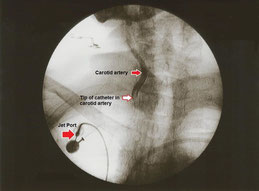

Röntgenbild eines arteriellen Katheters, der in die rechte Halsschlagader eingeführt wird, mit Markierungen für die Arterie und die Katheterspitze.

Kontrastbild eines arteriellen Katheters in der rechten Halsschlagader (Abbildung aus World Journal of Surgical Oncology (2018) 16:104, https://doi.org/10.1186/s12957-018-1404-8)